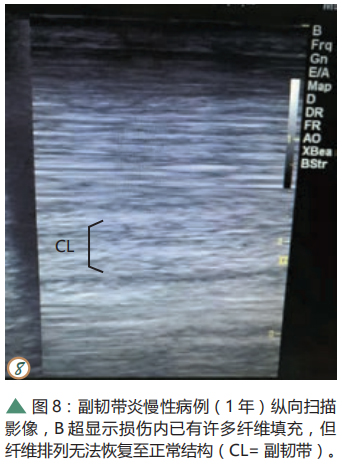

在獲得診斷以后應(yīng)制定一個康復(fù)訓(xùn)練計劃,在康復(fù)訓(xùn)練期間,患馬的活動應(yīng)嚴格受到控制,并且逐漸增加活動量,而不是將患馬放在草場任其自由活動,因為后者的做法可能導(dǎo)致副韌帶再次受損,使得損傷愈合的時間變長。建議在確診后間隔60天進行一次復(fù)查,并由獸醫(yī)根據(jù)患馬的跛行程度和B超檢查結(jié)果來評估是否可以增加活動量。慢性病例的纖維排列在B超中可能不會顯示出正常結(jié)構(gòu)(如圖 7、8),患部的腫脹可能會持續(xù)很長時間并且會逐漸形成堅實的纖維化增生(如圖 9、10)。